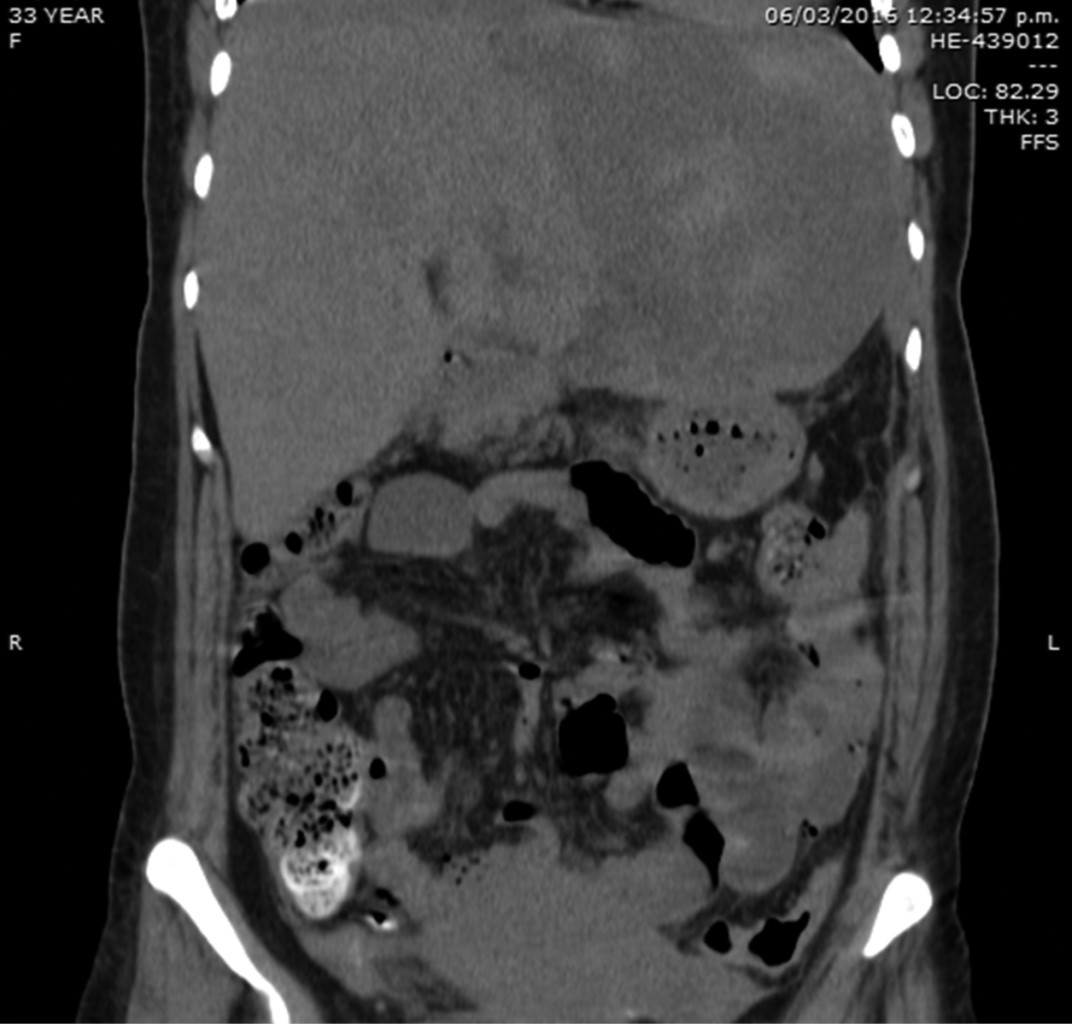

Se realiza USG obstétrico encontrándose producto único vivo con frecuencia cardiaca fetal de 140 latidos por minuto; se realizó operación cesárea de urgencia, obteniéndose producto único vivo y hallazgo de hematoma hepático subcapsular de aproximadamente 10 x 10 cm, por lo cual se realiza laparotomía exploradora en el mismo evento quirúrgico, con empaquetamiento hepático, con una hemorragia de 1,500 ml, ingresando posteriormente a la Unidad de Cuidados Intensivos hemodinámicamente estable, con presión arterial media superior a 70 mmHg. A las dos horas presentó choque hipovolémico, hipotensión arterial, con evidencia de sangrado, hemoglobina de 5.5 g/dl y plaquetas de 80,000 mm3, se realiza nueva exploración quirúrgica encontrándose hemoperitoneo de 1,000 ml y hemorragia hepática a nivel de ligamento redondo e intersección de ambos lóbulos, llevando a cabo nuevo empaquetamiento, reportándose durante el procedimiento sangrado de 1,000 ml. La paciente reingresa nuevamente a la Unidad de Cuidados Intensivos, hasta este momento contabilizándose transfusión de seis concentrados eritrocitarios, 10 bolsas de plasma fresco congelado y seis aféresis plaquetarias; se decide su envío a tercer nivel de atención ingresando a nuestro centro hospitalario en mal estado general, con apoyo mecánico ventilatorio, tensión arterial de 89/58 mmHg y hemoglobina reportada en gasometría arterial de 5 g/dl, así como datos de coagulopatía por consumo. Ingresa de forma directa a quirófano con hallazgos de hemoperitoneo de 1,500 ml y hematoma hepático subcapsular roto en lóbulo izquierdo grado III, se realiza ligadura de la arteria hepática común y arteria hepática izquierda accesoria, así como empaquetamiento hepático con cuatro compresas (Figura 1), se transfunden en el transoperatorio tres unidades de plasma fresco y cinco de concentrados eritrocitarios.

La paciente es trasladada a la Unidad de Cuidados Intensivos estable con presión arterial media de 70 mmHg, se realiza desempaquetamiento hepático a las 48 horas sin evidencia de sangrado activo, apreciándose hígado con adecuada consistencia, coloración, turgencia y con hematoma limitado (Figura 2). Veinticuatro horas después se retira el apoyo ventilatorio mecánico sin complicaciones, presentando adecuada evolución con tolerancia de la dieta, drenajes sin evidencia de sangrado activo; los exámenes de laboratorio a los siete días con hemoglobina de 11 g/dl, plaquetas de 332,000 y tiempos de coagulación dentro de parámetros normales, pruebas de funcionamiento hepático dentro de parámetros normales. Es egresada de la Unidad de Cuidados Intensivos estable, a los nueve días del postoperatorio presenta fiebre persistente, se realiza control tomográfico localizando amplia zona de necrosis en lóbulo hepático izquierdo y hematoma intraparenquimatoso de 15 x 10 centímetros (Figura 3), motivo por el cual se realiza nueva laparotomía exploradora con hallazgo de lóbulo hepático izquierdo necrótico y hematoma extenso de 1,500 ml (Figura 4); se realiza evacuación del hematoma, hepatectomía izquierda (Figura 5).